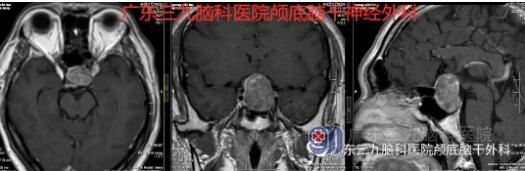

王先生的颅脑磁共振示鞍内-鞍上示一大小约25×22×30mm的团块状不均匀等短混杂T1等短长混杂T2异常信号影,增强扫描后呈不均匀强化,病灶包绕邻近左侧颈内动脉及部分右侧颈内动脉,鞍底下陷,鞍隔膨隆,视交叉及垂体柄受压。

鞍区占位性病变

术前MR